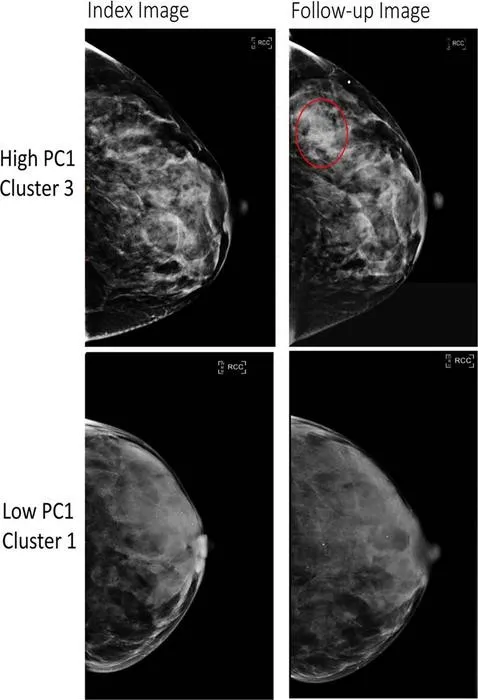

The new study, published in the journal Radiology, sought “a greater understanding of the distinct patterns and characteristics of breast tissue, beyond the measurement of breast density” and how that relates to breast cancer risk, states a press release.

To arrive at their findings, the researchers analyzed the mammograms of over 30,000 women without a prior history of breast cancer. From these images, they extracted 390 radiomic features (“patterns and characteristics that might not be visible to the human eye”), which they then grouped into six breast tissue patterns, scientifically known as phenotypes (“quantifiable characteristics or traits”).